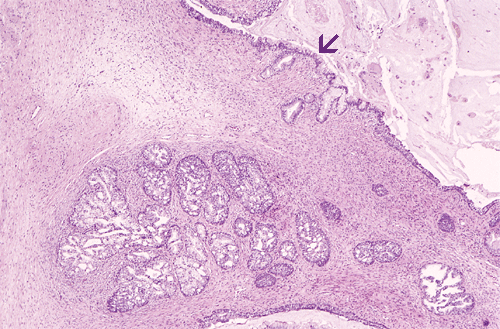

Histologic examination revealed complete replacement of lymph nodes by neoplastic tissue composed of mature mesenchymal, epithelial, and neural components associated with extensive fibrosis. A substantial amount of the tumor was composed of benign fibroblastic growth decorated by nests of epithelium with cyst formation. While most of the epithelial elements are that of intestinal or respiratory type (Panel A, arrow), a few small foci (less than 5%) appeared distinctly different. These foci consisted of small epithelial acini with a lobulo- centric arrangement (Panel A). The acini were composed of two cell types: cuboidal epithelial cells lining the lumens and smaller, more hyperchromatic cells located at the base of the acini. The epithelial cells showed proliferative features such as papillary luminal projections without fibrovascular cores, intraluminal bridging of these projections and mounds of pseudostratified cells (Panel B). These cells had abundant clear and granular cytoplasm. The nuclei were enlarged compared to the stromal cells, had fine chromatin pattern and occasionally had prominent nucleoli (Panel C). High molecular weight cytokeratin (34BE12) was expressed by the cells located at the periphery of these acini as a continuous or interrupted layer (Panel D). No immature teratoma elements or residual seminoma were noted in any of the lymph nodes.

Immunohistochemistry also disclosed strong expression of prostate specific antigen (PSA) and prostate specific acid phosphatase (PSAP) in the glandular elements. Prostatic lineage of these cells was thus confirmed. The histologic and immunohistochemical features of these epithelial cell nests were those of a high grade prostatic intraepithelial neoplasia (PIN). The differential diagnosis in this case included benign and neoplastic prostate tissue as well as other glandular tissues in mature teratoma. The morphology and immunohistochemical features, however, were diagnostic for a high grade PIN. There was no invasive adenocarcinoma of prostate in the metastatic mature teratoma.